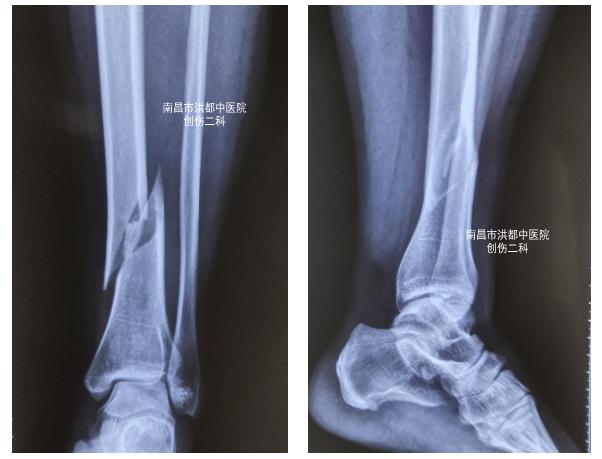

40岁的阿莲在家中不慎滑倒,导致 左小腿肿胀、疼痛 ,无法动弹。随即家人将她送到了南昌市洪都中医院就诊。创伤二科的医生立即给阿莲检查、拍片,经诊断: 左胫腓骨干骨折 ,也就是说阿莲左小腿大小两根骨头都断了。

术前DR

看到这个诊断结果,阿莲疑惑了,她问医生: “我才40岁,这么摔一下骨头就断了?!”医生解释道: “由于滑倒的冲击力度很大,发生事故的一瞬间力量集中在小腿上,就像拧毛巾一样把小腿骨头拧断了。”阿莲接受了受伤的事实,并详细询问了治疗方案和治疗效果后,决定住院接受手术治疗。